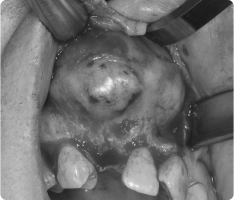

입안에도 혹처럼 불필요한 덩어리(종양)가 생길 수 있습니다.

그 중 흔히 볼 수 있는 것이 섬유종과 유두종입니다.

- 섬유종 : 잇몸, 뺨 안쪽, 혀 등에 자주 생기며, 오래된 자극(씹힘, 틀니, 교정 장치 등) 때문에 발생하는 경우가 많습니다.

- 유두종, 사마귀종 : 바이러스 감염이나 잦은 자극으로 인해 작은 사마귀처럼 돌출되는 양상을 보입니다.

대부분 양성(암 아님) 이지만, 크기가 커지거나 불편하면 제거하는 것이 좋습니다.

- 국소마취 후 병소 부위를 작게 절개하여 종양만 제거합니다.

- 필요한 경우 조직검사를 통해 정확한 진단을 확인합니다.

- 수술은 짧고 안전하게 진행되며, 회복도 빠릅니다.